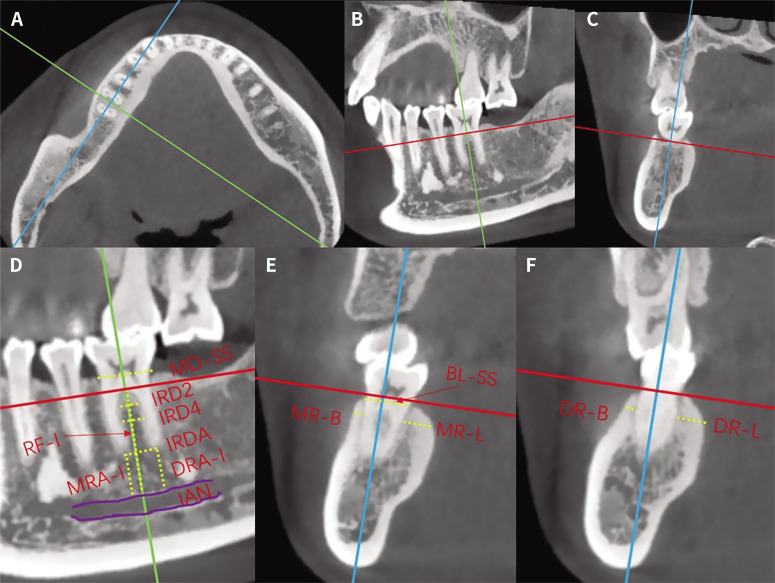

Purpose: This cone-beam computed tomography (CBCT) study aimed to analyze the anatomical characteristics of alveolar bone at mandibular first molar (MFM) and their implications for immediate implant placement surgery.

Materials and methods: 100 patients with 140 MFMs were reviewed retrospectively. We first performed a 3D reconstruction of the patient's CBCT data to determine a reference plane with ideal implant placement and orientation. The following parameters of MFM region were analyzed: mesial-distal socket size (MD-SS), buccal-lingual socket size (BL-SS), root furcation fornix to inferior alveolar nerve (IAN) distance (RF-I), interradicular bone thickness (IRB), mesial/distal root apex to the IAN distance (MRA-I/DRA-I), thickness of the buccal/lingual bone of the mesial root (MR-B/MR-L), thickness of the buccal/lingual bone of the distal root (DR-B/DR-L).

Results: The MD-SS of MFM was 8.74 ± 0.76 mm, and the BL-SS was 8.26 ± 0.72 mm. The MR-B, DR-B was 1.01 ± 0.40 mm and 1.14 ± 0.50 mm, and the difference was statistically significant (P = .001). The values of the MR-L, DR-L were 2.71 ± 0.78 mm and 3.09 ± 0.73 mm, and the difference was also statistically significant (P < .001). The mean distance of RF-I was 15.68 ± 2.13 mm, and the MRA-I was 7.06 ± 2.22 mm, which was greater than that of DRA-I (6.48 ± 2.30 mm, P < .001). The IRB at 2 mm, 4 mm apical from the furcation fornix, and at apex level was 2.81 ± 0.50 mm, 3.30 ± 0.62 mm, and 4.44 ± 1.02 mm, respectively.

Conclusion: There is relatively sufficient bone mass in interradicular bone in height, but an adequate width is lacking for the bone between the mesial and distal root after the extraction of the MFM for immediate implantation. The thickness of the MFM buccal bone is relative thin, especially for the mesial root.